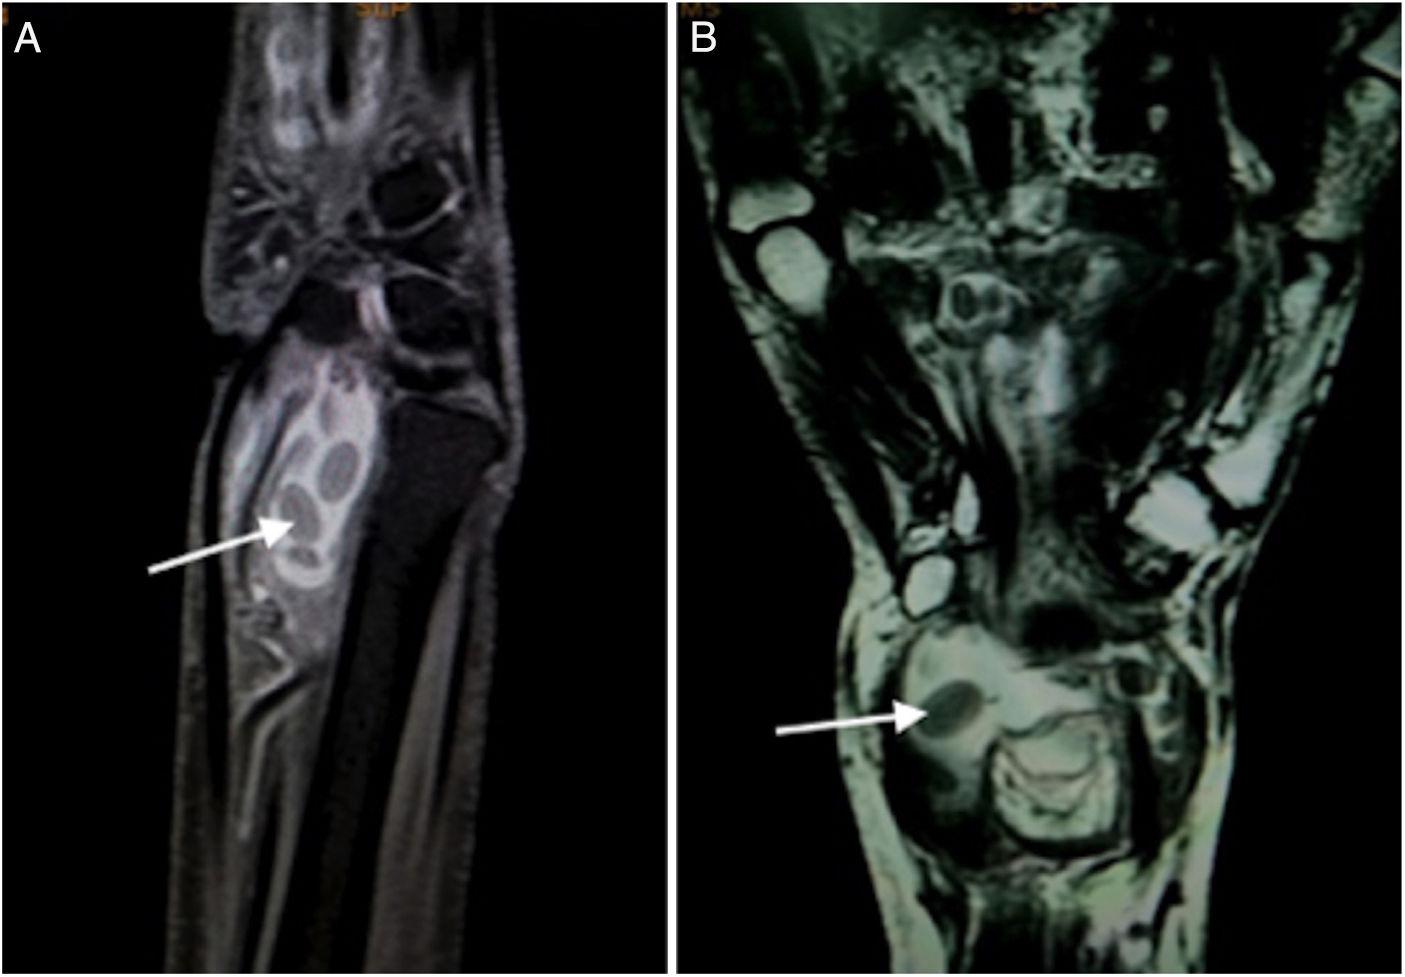

Rice Bodies in Tuberculous Tenosynovitis of Wrist Reumatología Clínica What Is A Rice Body the meaning of rice body is any of the smooth glistening ovoid particles resembling grains of rice that occur in joints and the. They are located in the synovial fluid,. the video reviews the pathogenesis, diagnosis, and management of rice bodies in the articular space of the shoulder and discusses the case. What Is A Rice Body.

Rice Bodies by Tenosynovitis of the Wrist A Case Report What Is A Rice Body the meaning of rice body is any of the smooth glistening ovoid particles resembling grains of rice that occur in joints and the. the video reviews the pathogenesis, diagnosis, and management of rice bodies in the articular space of the shoulder and discusses the case. They are located in the synovial fluid,. What Is A Rice Body.

Tuberculous Tenosynovitis of Ankle with Rice Bodies The Foot and What Is A Rice Body the meaning of rice body is any of the smooth glistening ovoid particles resembling grains of rice that occur in joints and the. They are located in the synovial fluid,. the video reviews the pathogenesis, diagnosis, and management of rice bodies in the articular space of the shoulder and discusses the case. What Is A Rice Body.

Tuberculous Tenosynovitis of Ankle with Rice Bodies The Foot and What Is A Rice Body They are located in the synovial fluid,. the meaning of rice body is any of the smooth glistening ovoid particles resembling grains of rice that occur in joints and the. the video reviews the pathogenesis, diagnosis, and management of rice bodies in the articular space of the shoulder and discusses the case. What Is A Rice Body.